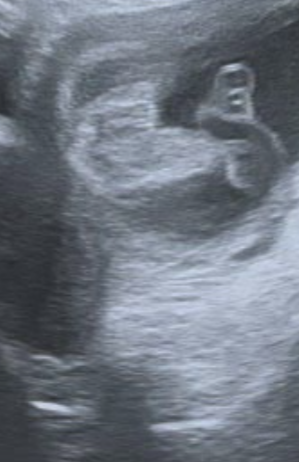

Dobrý denKolik dní to je podle velikosti reálné po ovulaci?Děkuji

Dobrý den,

jedná se o velmi časnou fázi těhotenství, přesně stáří Vám takto nelze říct, nicméně vzhledově embryo odpovídá cca 6.-7. gestačnímu týdnu.